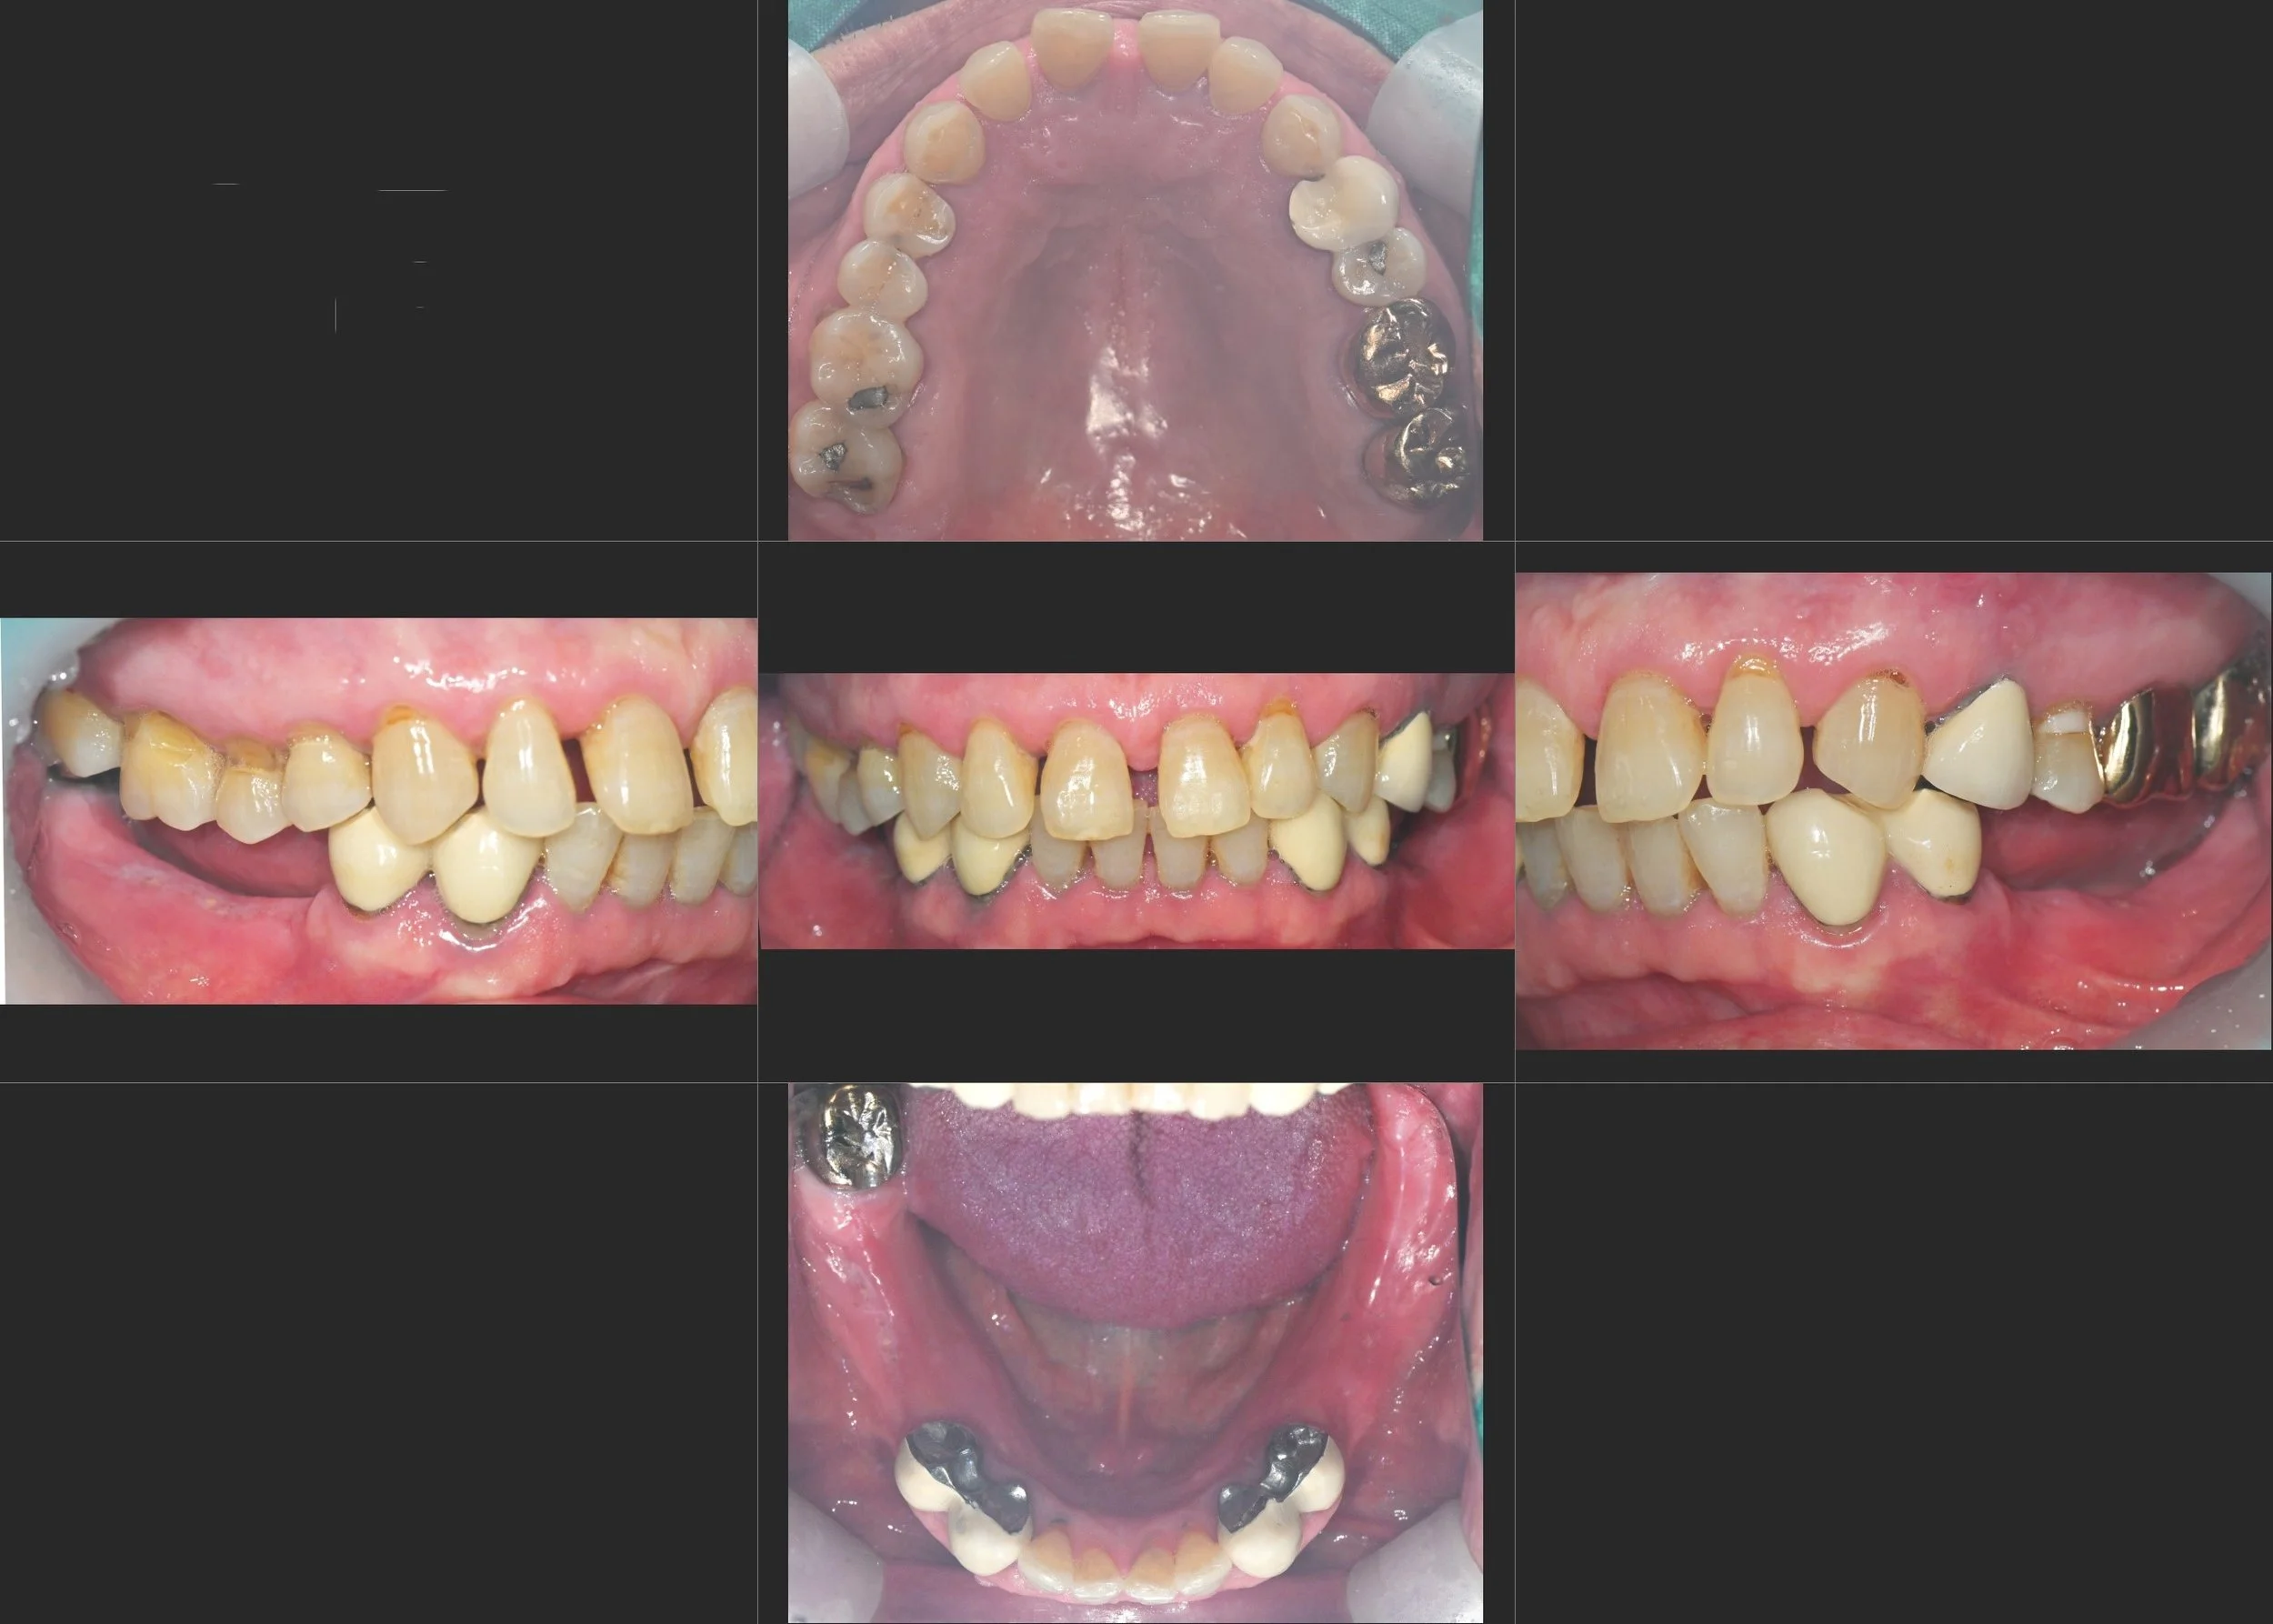

OPG - BEFORE

INTRA ORAL - BEFORE